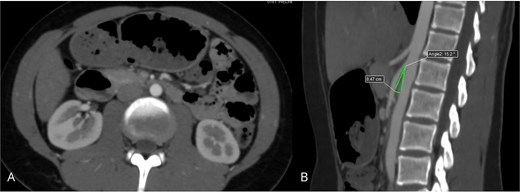

Contrast-enhanced abdominal CT with angiographic reconstruction demonstrated narrowing of the aortomesenteric angle to 17°, resulting in compression of the third portion of the duodenum (Fig. 1). Upper gastrointestinal endoscopy showed extrinsic pulsatile compression of the third duodenal portion, with no mucosal abnormalities. Based on these findings, a diagnosis of SMAS was confirmed.

Contrast-enhanced abdominal CT demonstrating compression of the third portion of the duodenum: (A) axial view showing duodenal dilatation and abrupt narrowing; (B) sagittal reconstruction revealing a reduced aortomesenteric angle of 17°.